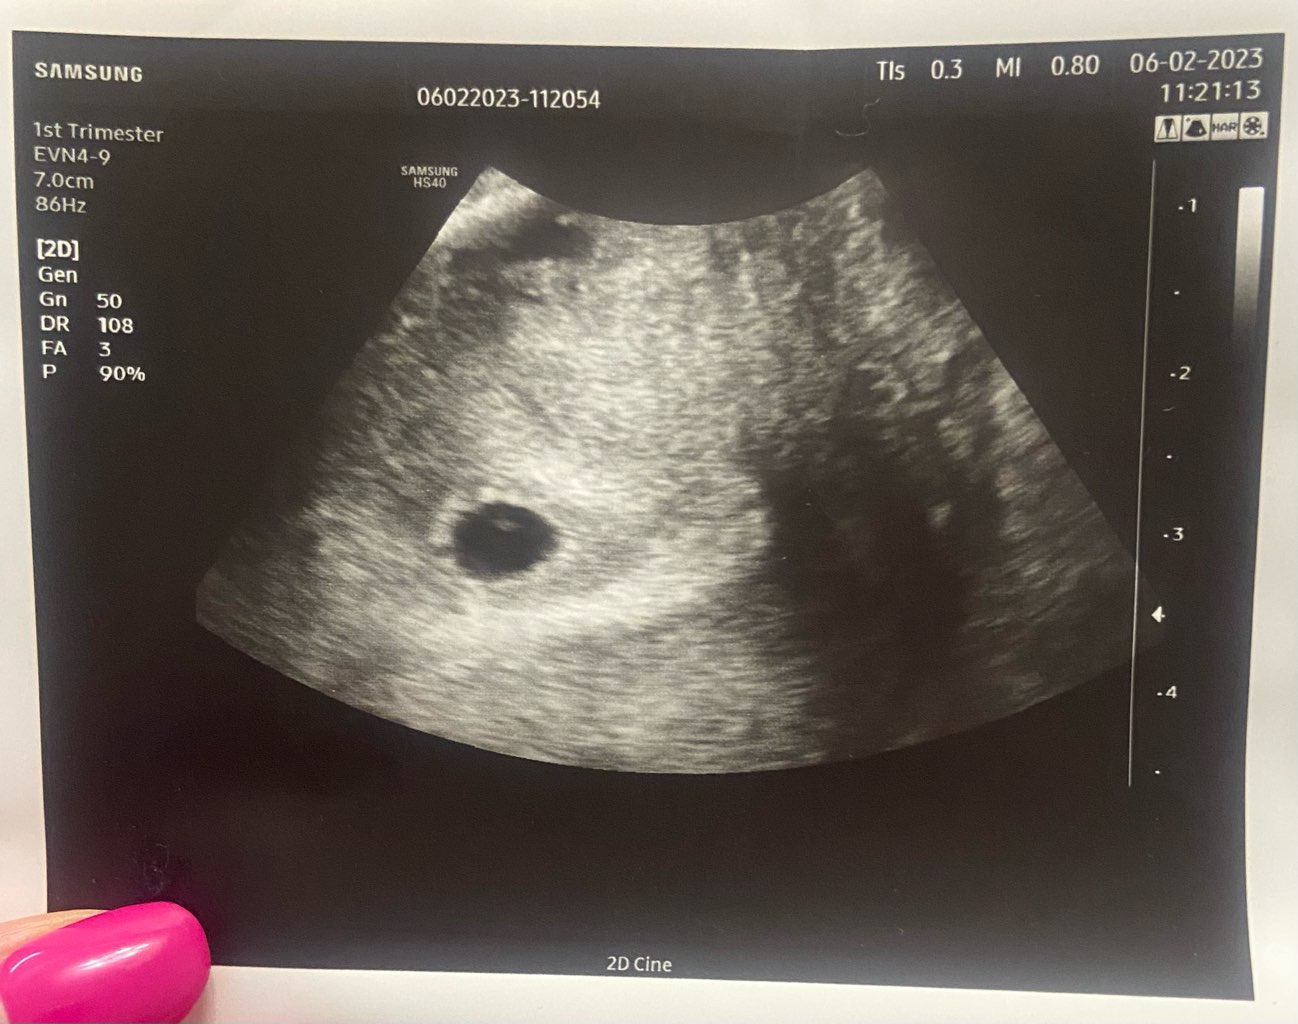

Super, gratulacje!Jest zarodek 0,34 cm i widoczna akcja serca![]()